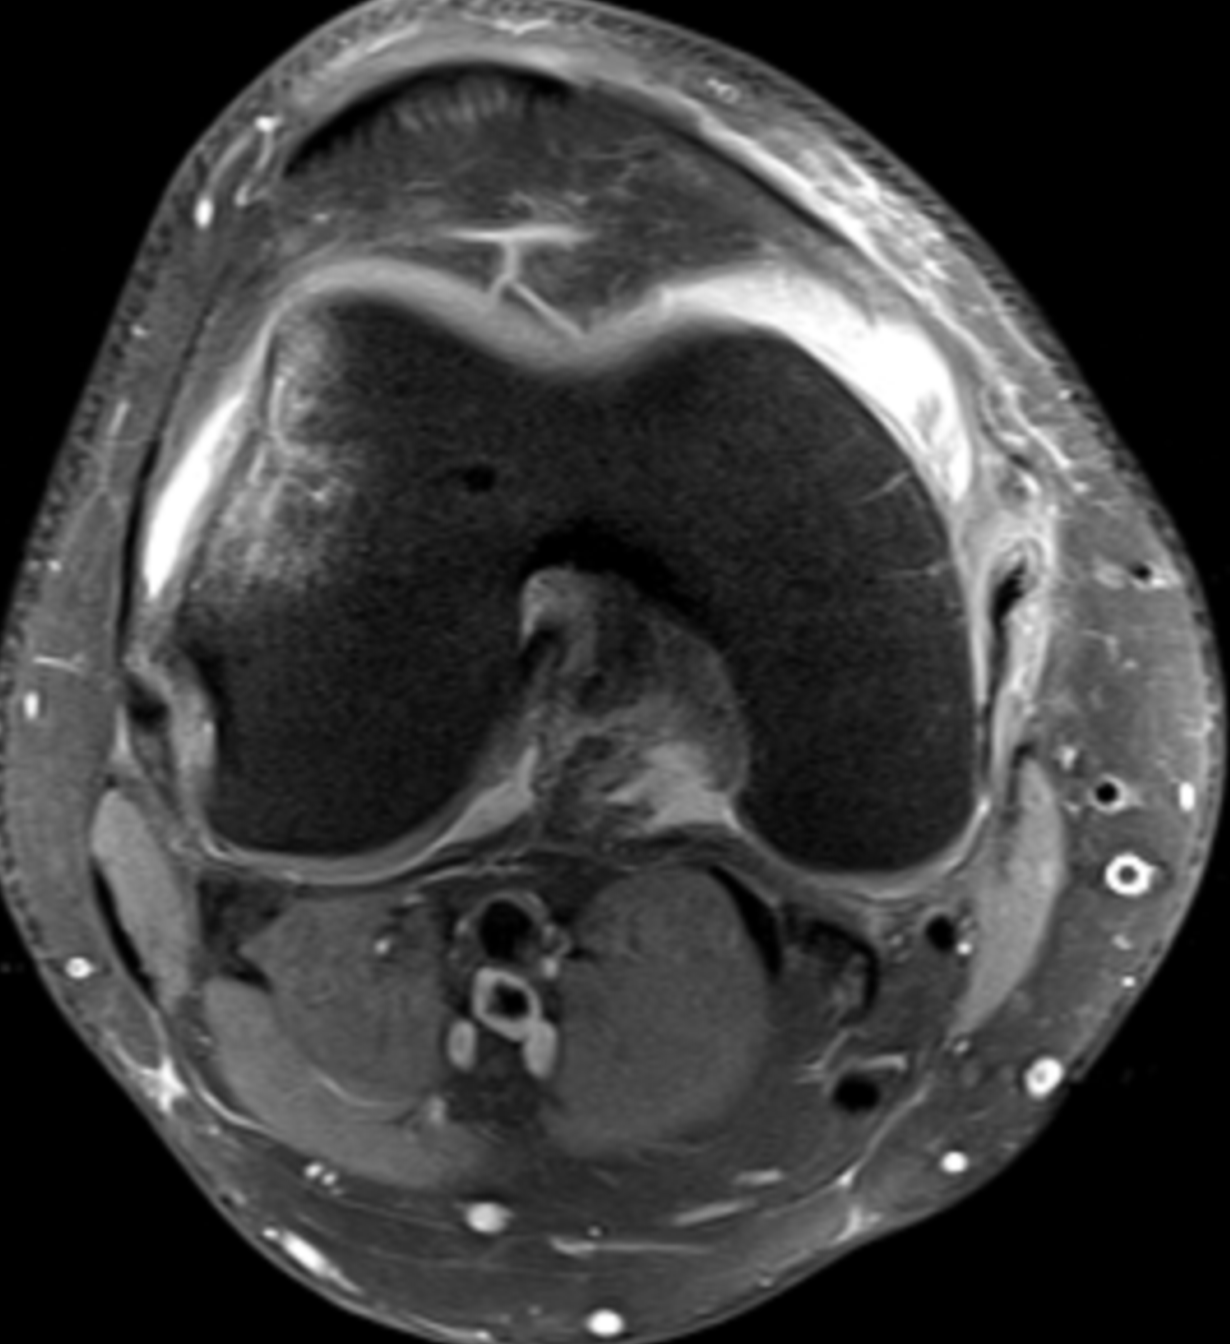

PD FS Axi: Transient patellar dislocation with typical subcortical lateral femoral condyle contusion and a tear of the medial patellar femoral ligament (MPFL). The MPFL tear is located posteriorly near its junction with the medial collateral ligament.

PD FS Axi: Grade IV chondral injury of the lateral aspect of the patellar articular surface is noted. Wiberg type III patella (markedly smaller medial patellar facet) is seen; predisposing factor for patellofemoral dislocation. Large amount of subsequent suprapatellar fluid collection.